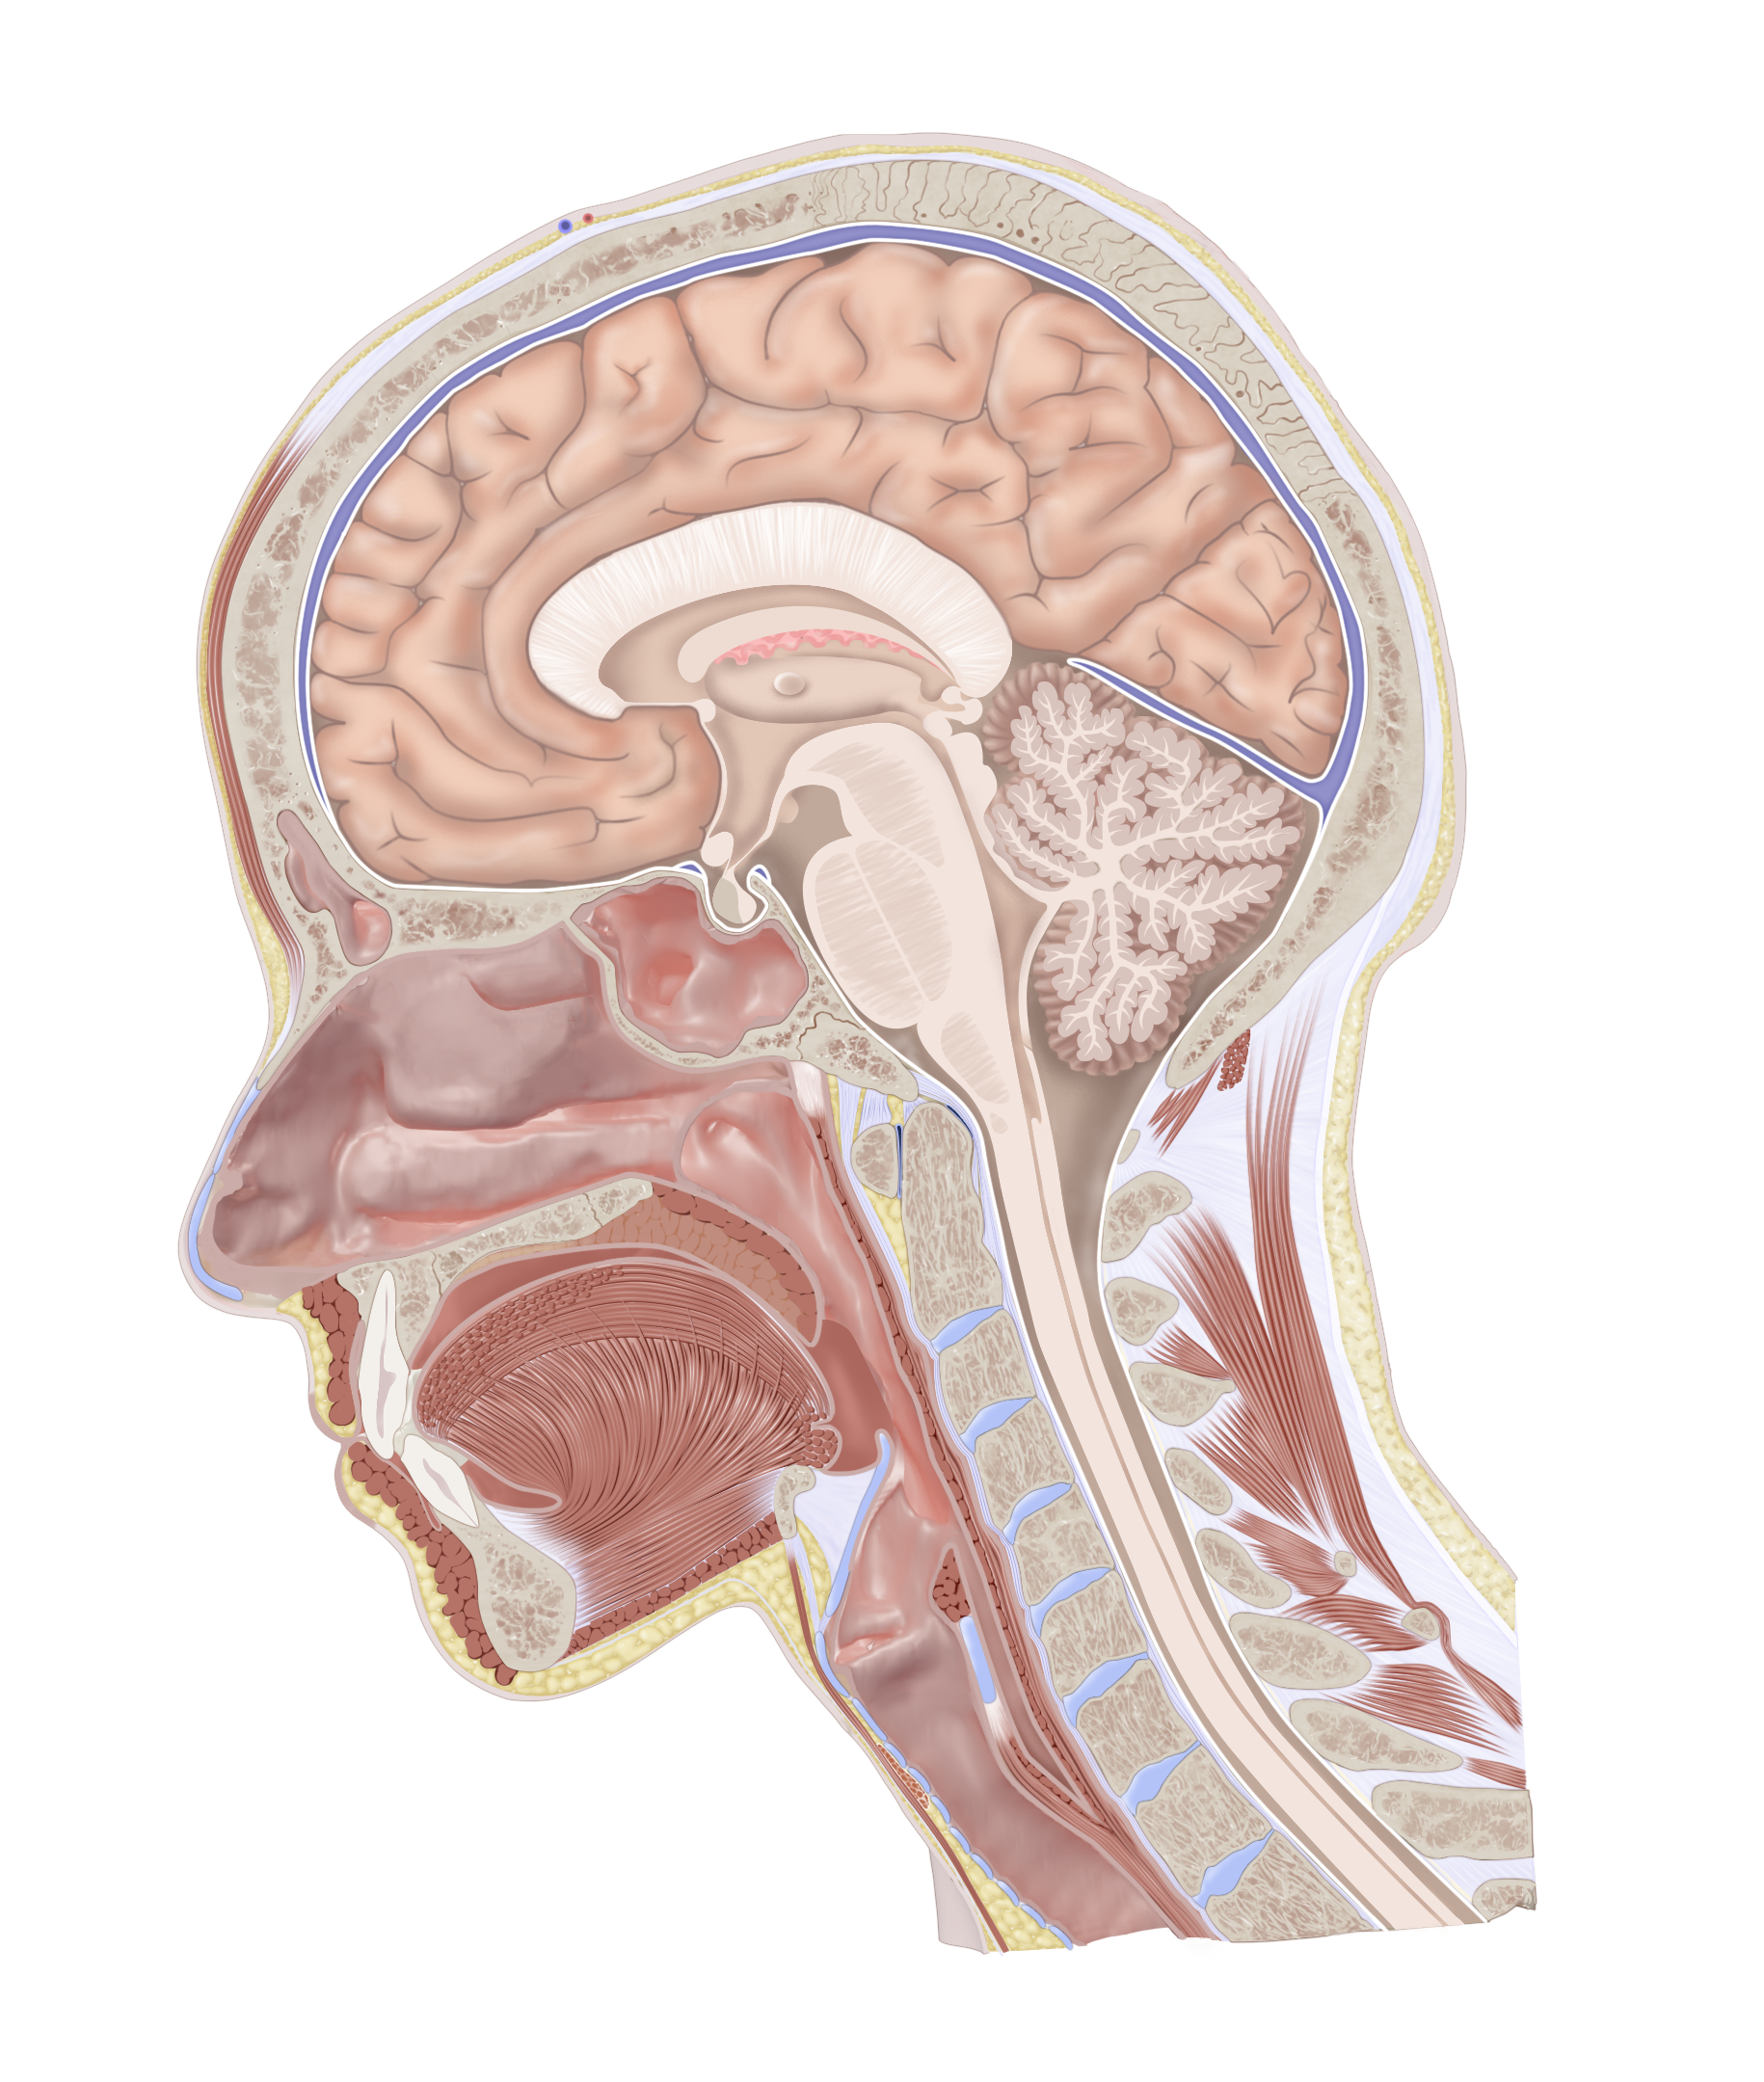

Uninjured Head Cross Section

Demonstration of normal anatomy before accident. Created from CT using 3D modeling and Photoshop.